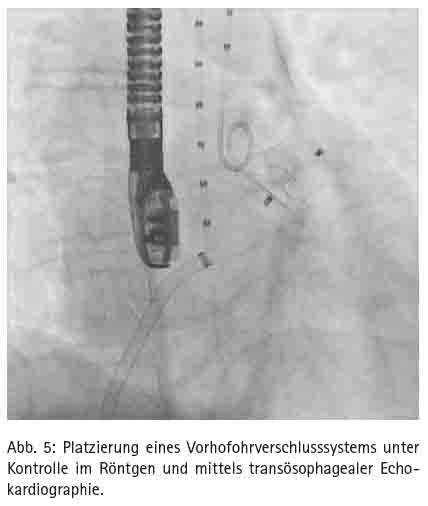

Der Eingriff erfolgt im Herzkatheterlabor unter Röntgendurchleuchtung und transösophagealer Echokardiographie und dauert ca. 60 Minuten (Abb. 5). Wegen der transösophagealen Echokardiographie ist eine Analgo-Sedierung oder intravenöse Kurznarkose sinnvoll. Der Zugang erfolgt über eine Leistenvene. Anschließend wird eine transseptale Punktion durchgeführt. Dann wird selektiv ein Katheter in das linke Vorhofohr vorgeführt und eine Angiographie in mehreren Ebenen zur Größenbestimmung und Beurteilung der Anatomie durchgeführt. Nach der ermittelten Größe und anatomischen Vorgabe erfolgt die Deviceauswahl. Derzeit stehen folgende drei Occluder zur Verfügung: Watchman, Amplatzer Cardiac Plug und Amulet. Im Weiteren wird die Device-Schleuse im linken Vorhofohr positioniert. Durch die Schleuse wird das gefaltete Device in das Vorhofohr vorgeschoben und freigesetzt. Eine orale Antikoagulation ist als Nachbehandlung nicht mehr nötig. Die Patienten erhalten nach individueller Maßgabe für die drei bis sechs Monate eine duale Thrombozytenaggregationhemmung. Eine antibiotische Endokarditisprophylaxe sollte für sechs Monate durchgeführt werden.